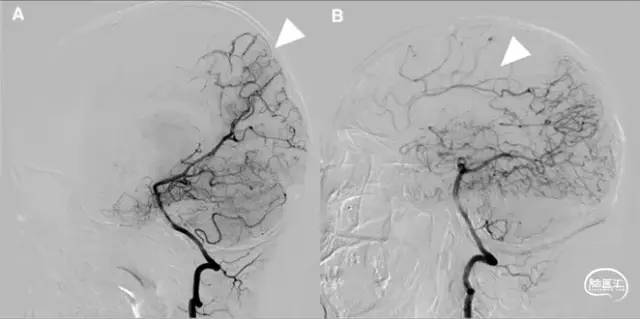

图1 从大脑后动脉(PCA)到大脑前动脉(ACA)的软脑膜侧支;A. 椎动脉注射侧位图显示ACA和PCA区域之间的逆行血流(PCA→ACA顶枕支)延伸到皮质边界区;B. 经后胼胝体周动脉经中央沟的血供。[7]